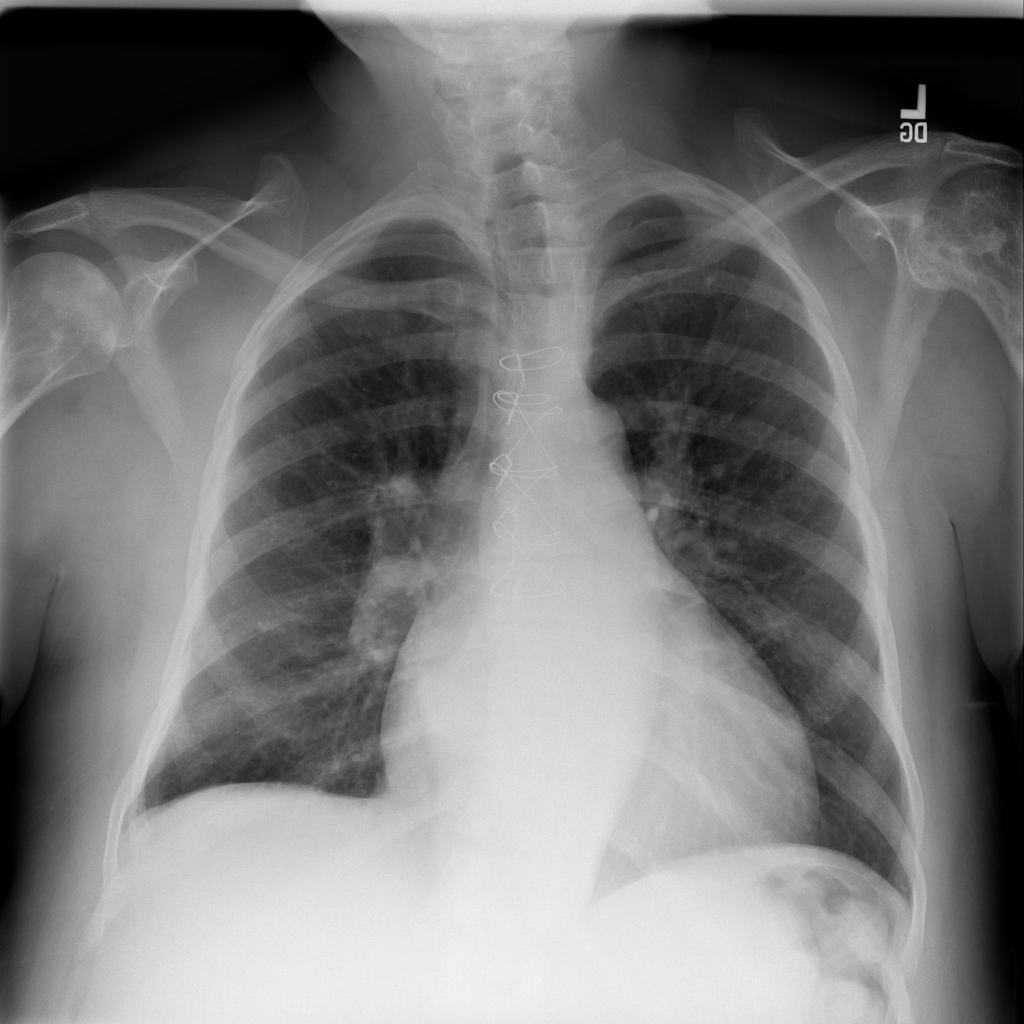

PAT-4639 · IMG-045Cardiomegaly

PAT-4639 · IMG-045

PA